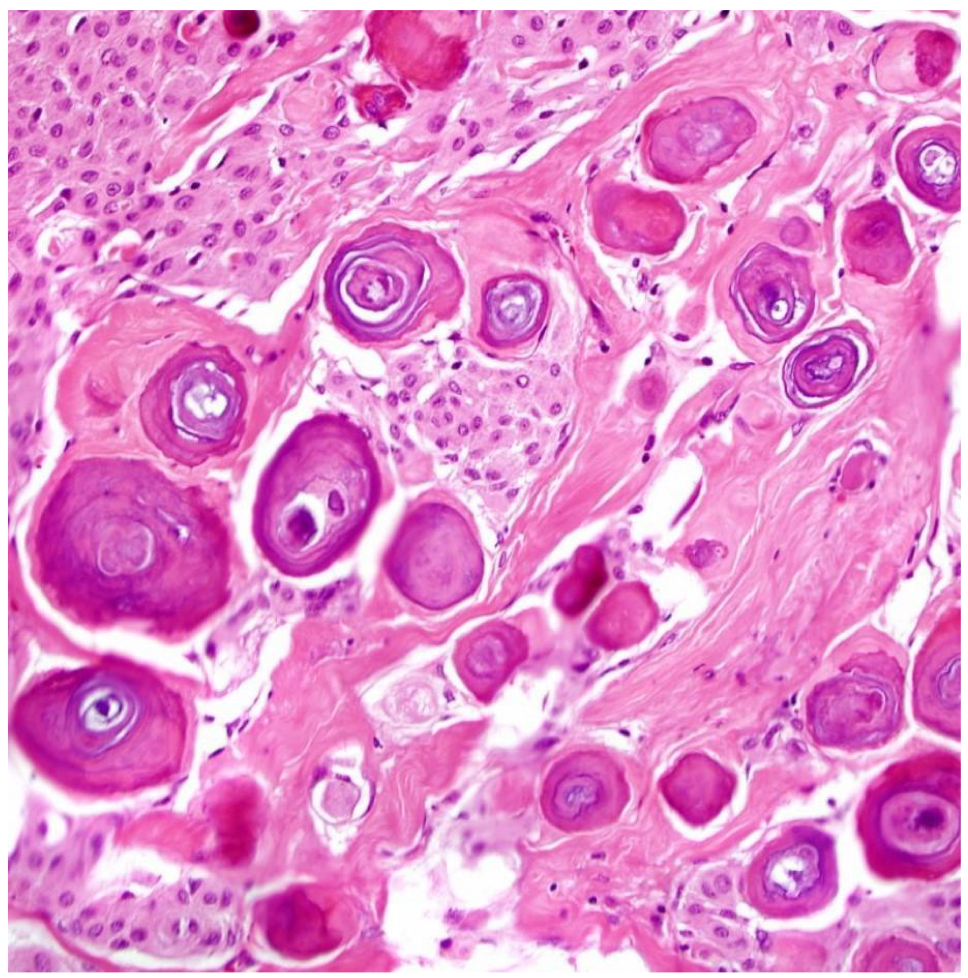

“well” differentiated: close resemblance to parent cell

> for squamous epithelium: ability to form keratins